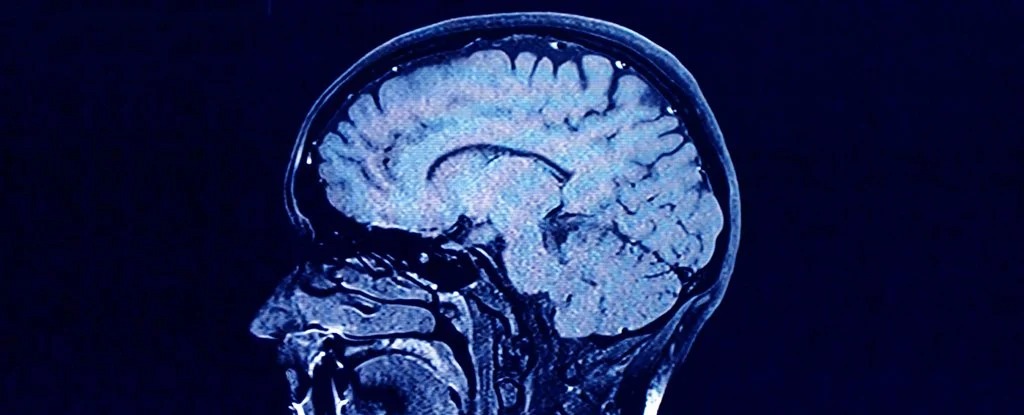

How Anorexia Could Change The Structure Of Your Brain